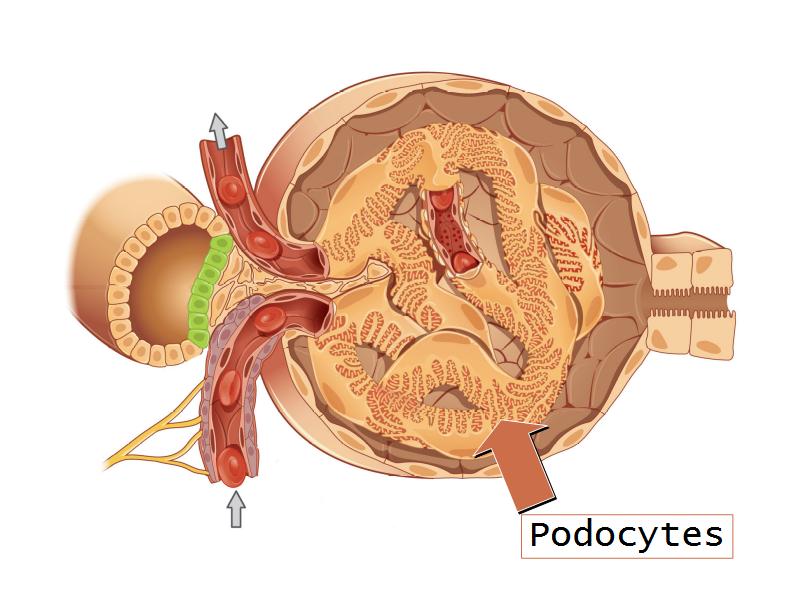

- Basic anatomy of the kidney

- Basic arrangement of nephrons and collecting tubules in the kidney

- Structure of the nephron and collecting tubules

- The renal corpuscle

- Make an annotated diagram of a nephron, including the juxtaglomerular apparatus. Indicate the flow of blood and water in each part, and how solutes are filtered, secreted and reabsorbed.